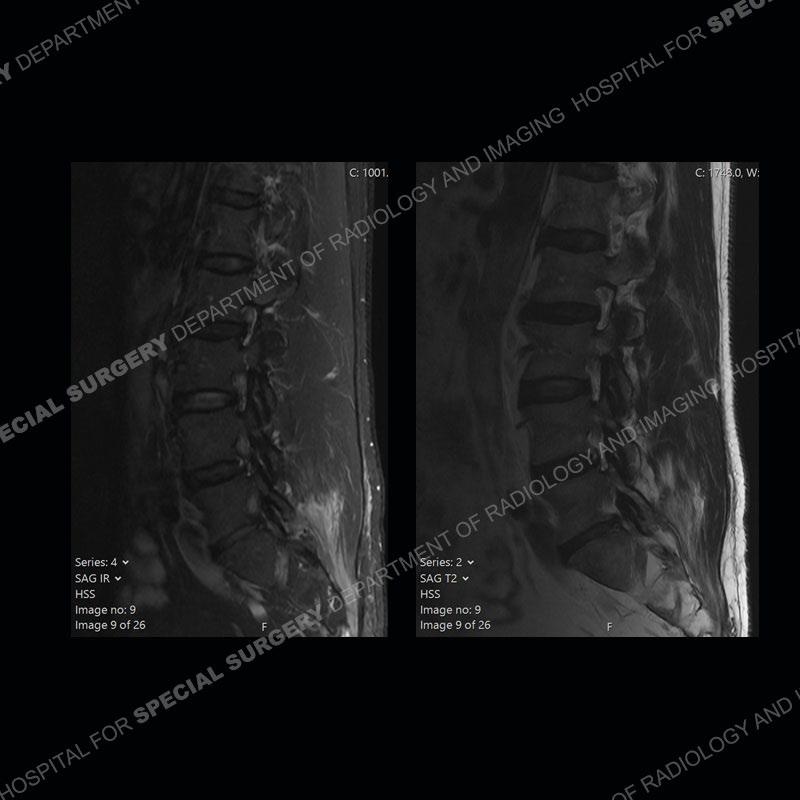

Post operative changes are seen on the left side at L5-S1 where there is near complete removal of the left sided L5 lamina, partial resection of the left L5-S1 facet joint, and resection of the left sided ligamentum flavum. In the anterolateral epidural space about the subarticular recess is a mass that demonstrates similar T1 and T2 signal characteristics to the adjacent degenerated disc. There is enhancement about the periphery of the mass, but the majority of this somewhat geographic or polyploid mass demonstrates no enhancement. The mass exerts prominent mass effect on the left S1 axillary sleeve/proximal nerve root. The left S1 nerve root shows enlargement and increased enhancement as compared to the contralateral right side.